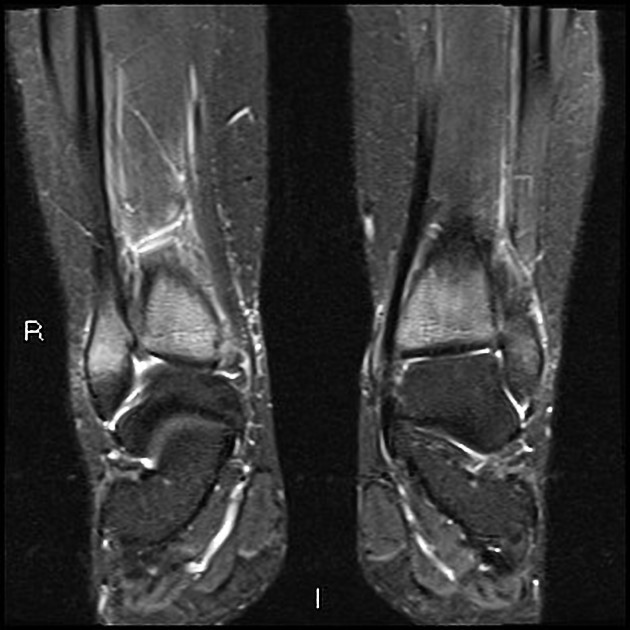

Synovial chondromatosis

synovial proliferation leading to multiple cartilaginous loose joint bodies–some ossify

1*– 4th-5th decades, M >F, unknown cause, Knee>Hip>elbow>shoulder

2*– to degenerative changes, fewer and larger fragments, older population, other degenerative findings\